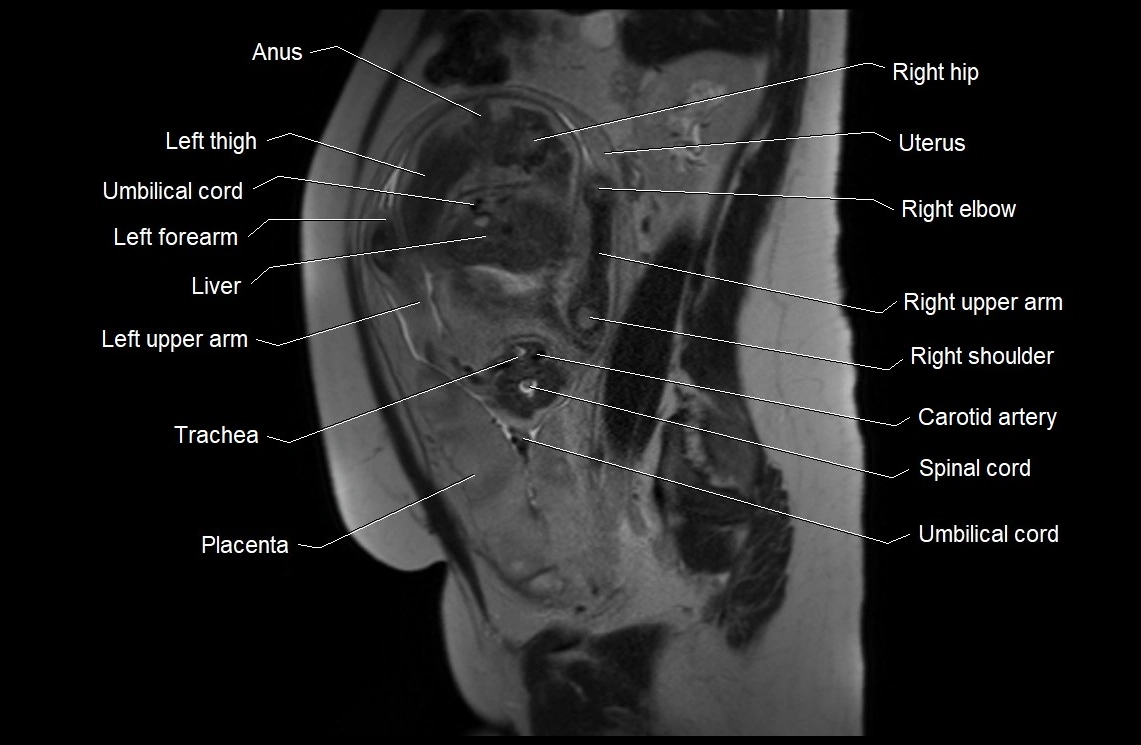

MRI Appearance

T2 HASTE (T2 GRE):

• Amniotic fluid shows very bright hyperintense signal

• Provides natural contrast against fetus and placenta

• Small particles (vernix) may appear as scattered hypointense foci within bright fluid

MRI image

image